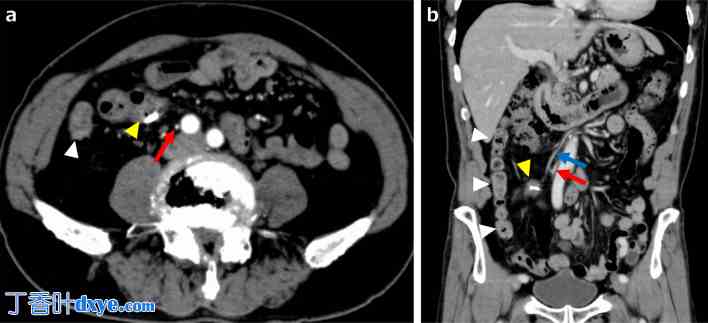

图 3.

增强 CT 图像。a 轴向 CT 图像显示夹持器位于右侧降结肠(黄色箭头),IMA 对称走行(红色箭头),乙状结肠位于右侧(白色箭头)。 b 矢状位 CT 图像显示右侧降结肠夹(黄色箭头)和右侧固定的乙状结肠(白色箭头),以及 IMA(红色箭头)和 IMV(蓝色箭头)的对称走行。